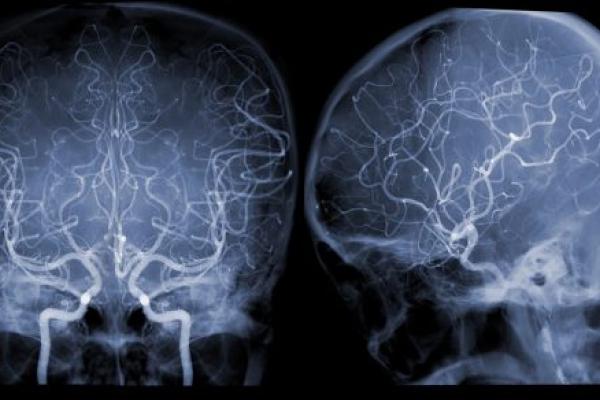

Our doctors and researchers are experienced in every area of neurosurgery. We’re among the best centers in the world with the latest approaches in minimally invasive surgery, neuro-endovascular surgery, Gamma Knife radiosurgery, robotic assisted surgery, deep brain stimulation surgery, laser interstitial therapy and other modalities for the treatment of brain, spine and peripheral nerve disorders and disease. You can get care for a full range of conditions, from traumatic brain injuries and stroke to epilepsy, Parkinson’s disease and more.

We use sophisticated imaging and testing approaches to find disease and develop a treatment plan that gives you the best possible results. We make sure you and your family are well-informed about your condition, treatment and recovery. We also connect you with other professionals as needed, such as mental health specialists, rehabilitation specialists, pain management experts and supportive services. We consider all your needs to ensure you receive the very best care.

Penn State Health is continually looking for breakthroughs in treating nervous system tumors, repairing nerve damage and neurosurgery. We’ve become a national leader in studies on quality of life for both patients and their caregivers. Our research efforts focus on ALS, peripheral nerve tumors, brain tumors, brain aneurysms, tumor growth, stroke and nerve damage. You can get some of today’s most promising treatments before they become widely available. Learn more about our clinical trials.

• Cerebrovascular neurosurgery

• Endovascular neurosurgery

• Vascular neurosurgery